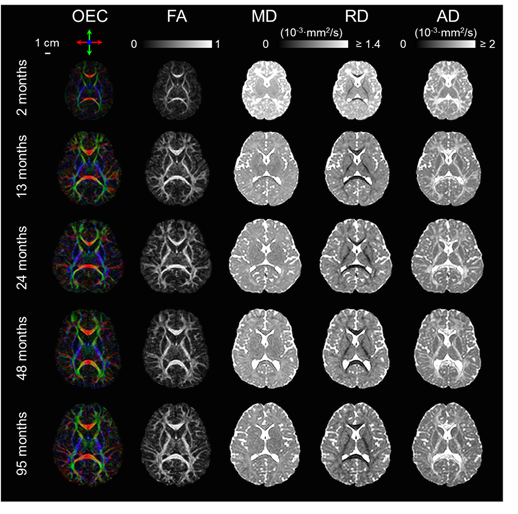

In previous studies, insufficient sample covering the critical development period from birth to early childhood brings enormous difficulty to quantify white matter development. To cover the deficiencies, we acquired DTI data from a larger sample size, 118 typically developing (TD) children, at the age with critical development, which is from 0 to 8 years. Fig. 2 illustrates the DTI metrics changes in the white matter from 2 to 95 months. At this period, the brain volume increased, white matter FA increase, MD and RD decreased.

Fig. 2, Changes of orientation-encoded colormap (OEC), FA, MD, RD, and AD from 2 to 95 months